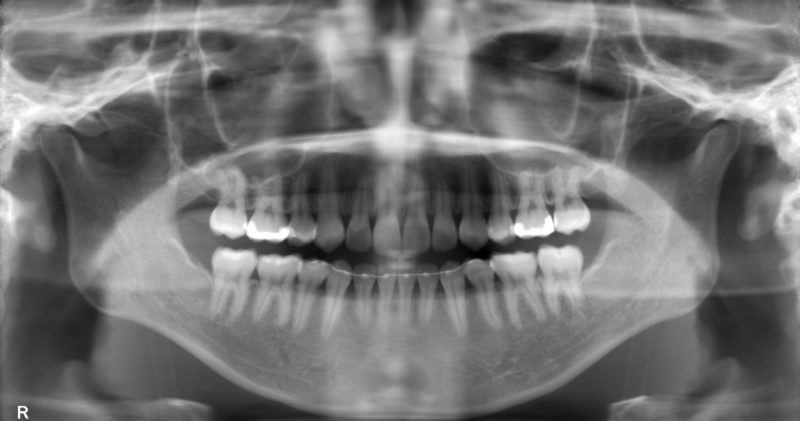

なかでも、エックス線検査(レントゲン撮影)によって発見された埋伏過剰歯は、その場所の歯の並びに関係することがあります。とくに、隣り合う永久歯の生える方向、あるいは歯の根っこの形成を障害する可能性がある場合は過剰歯の摘出が必要となります。

乳歯の先天性欠如(せんてんせいけつじょ・生まれつき特定の歯がないこと)はまれですが、パノラマレントゲンなどで永久歯の先天性欠如が見つかることがあります。欠如した永久歯の部分に生えている乳歯が抜けずに永久歯列期になっても存在しつづける場合や、抜けてしまった場合にはすき間が発生します。

上記にあげたように、混合歯列期における予防は不正咬合の原因となる項目に対する処置に加えて、乳歯から永久歯への交換が円滑に進むように助ける効果もあります。問題発見には、この時期のパノラマエックス線写真による検査が重要となります。